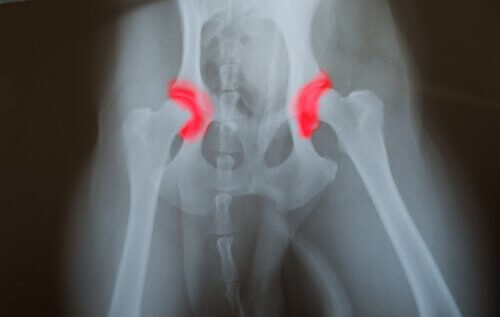

形成異常とは?

腰やひじの形成異常は遺伝的な病気で、世代から世代へと受け継がれます。この形成異常は腰やひじの関節が正しく位置していないことにより起こります。骨が互いにぶつかり合い、不自然な動きをしてしまうので骨の摩耗が速くなり、関節がうまく機能しなくなるような問題が起こります。この病気の問題は、これがひっそりと進行することです。

つまりこの問題が例えば生まれつきなど長い間存在していても、より後の段階になるまで痛みを感じることが無いということです。あなたがこれに気づくころには、普通に食べたりジャンプしたりしていた犬がほぼ完全に動けなくなってしまっているのです。

犬の中には、遺伝的な構造のためにこの病気になりやすい犬種もあります。特に大型犬に多く、その原因は関節が重い体重を支えなければならないからだと言われています。また、体の成長が速い犬なども、関節が強化されるのが間に合わないためこの病気にかかりやすくなります。